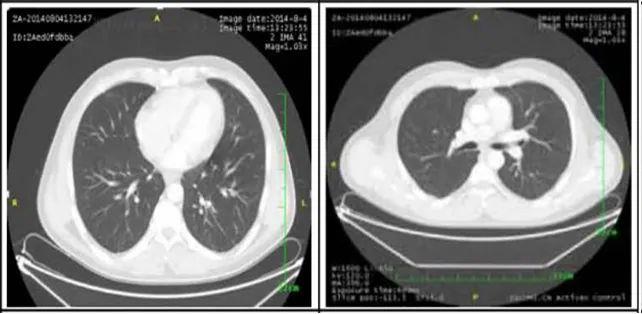

2. 肺部病灶治疗前后核磁对比:

肺部转移病灶在用药后2个月明显缩小,4个月后病灶基本消失。

治疗前

治疗2个月